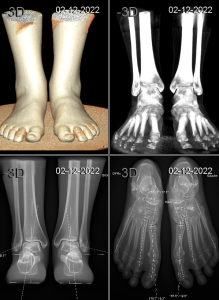

Il s’agit d’un appareil type cone beam permettant d’étudier en position débout, comme un scanner, les pieds, les chevilles et les genoux avec une très faible irradiation du patient comparé à un scanner conventionnel.

Le patient est debout et l’appareil tourne autour de ses pieds sans entrer en contact avec lui.

Il suffit de moins d’une minute pour obtenir une acquisition volumique 3D des pieds et des chevilles.